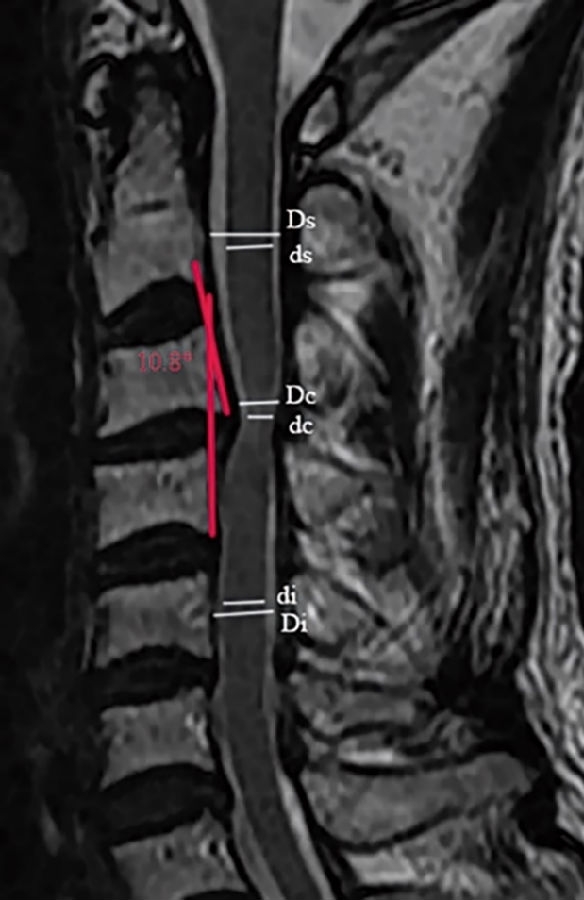

3.1颈椎MRI矢状位脊髓压迫比值

依据Fehlings等报道的方法测量颈椎MRI矢状位脊髓压迫比值(compression ratio of the spinal cord,CRS)。分别测得颈椎MRI矢状位,压迫程度最重节段脊髓直径(dc),上方椎体水平非压迫节段脊髓直径(ds)以及下方椎体水平非压迫节段脊髓直径(di)(图1)。其中选择MRI正中矢状位或旁矢状位测量,依据颈椎间盘压迫位置,分为中央型与旁中央型。CRS具体测量公式如下:

3.2 颈椎间盘突出程度

颈椎间盘突出程度依据颈椎MRI矢状位椎管压迫比值(compression ratio of the cervical spinal canal,CRCS)。椎管压迫比值CRCS与脊髓压迫比值CRS测量方法类似,只是前者测量的是椎管整体压迫程度,后者关注的是脊髓本身压迫程度。分别测得颈椎MRI矢状位压迫程度最重节段椎管直径(Dc),上方椎体水平非压迫节段椎管直径(Ds)以及下方椎体水平非压迫节段椎管直径(Di)(图1)。CRCS具体测量公式如下:

之后依据CRCS比值,将患者分为间盘严重突出组(CRCS>30%)及间盘非严重突出组(CRCS≤30%)。

图1.颈椎MRI矢状位脊髓压迫比值和颈椎间盘突出程度的测量方法。颈椎MRI矢状位,压迫程度最重节段脊髓直径(dc),上位椎体水平非压迫节段脊髓直径(ds)以及下位椎体水平非压迫节段脊髓直径(di);压迫程度最重节段椎管直径(Dc),上位椎体水平非压迫节段椎管直径(Ds)以及下位椎体水平非压迫节段椎管直径(Di)

颈椎节段后凸角度测量使用Harrison椎体后切线法,此测量方法相较Cobb角法对颈椎后凸的评估更可靠。本研究中,我们尝试探索退变性颈椎后凸对神经功能的影响,Harrison椎体后切线法更直接评估椎体后缘成角而非椎体上下终板交角对脊髓的影响,可能会提高测量结果与脊髓神经功能损害程度的相关性(图1)。分别测量了在颈椎MRI矢状位像上、颈椎侧位X线、过屈位X线及过伸位X线上的颈椎节段角度。本研究中颈椎前凸角度定为负值,颈椎后凸角度定为正值,以°为标准界定颈椎后凸。